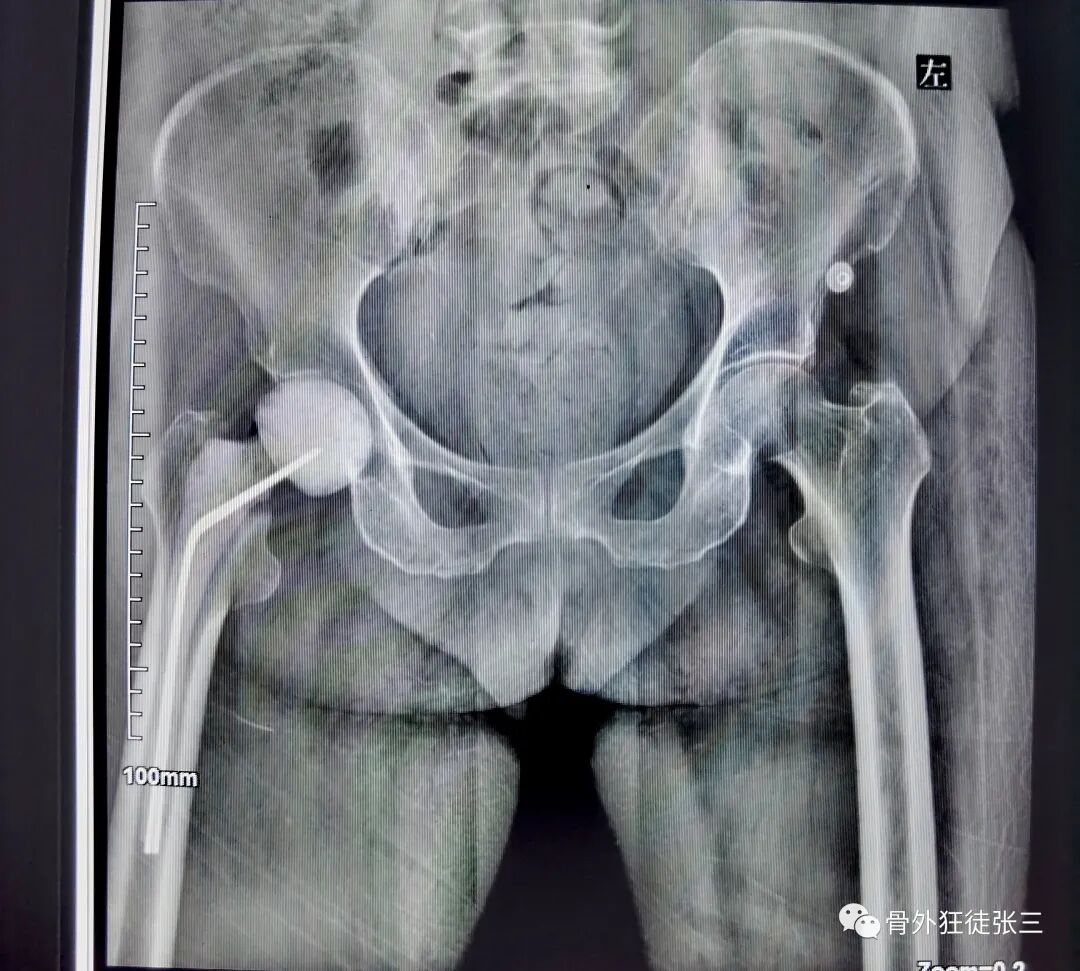

病例42,人工股骨头置换术后感染,spacer置入